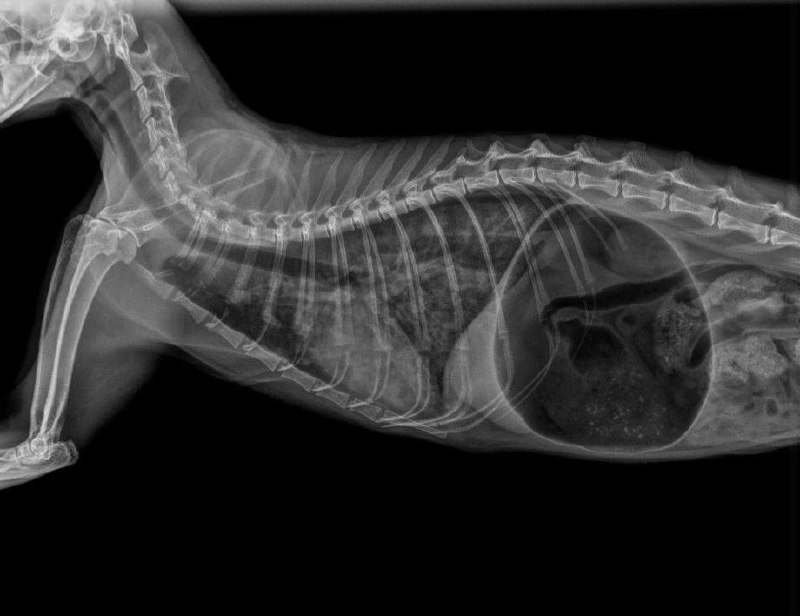

В клинику «ТерраВЕТ» на Советской в критическом состоянии попал котик Перси, которому всего 3 года. У него были признаки отека легких и острого расширения желудка.

У героя нашей истории был кардиогенный отек легких, вызванный врожденными заболеваниями сердца, а также осложненный бронхитом, который врачи выявили на КТ.